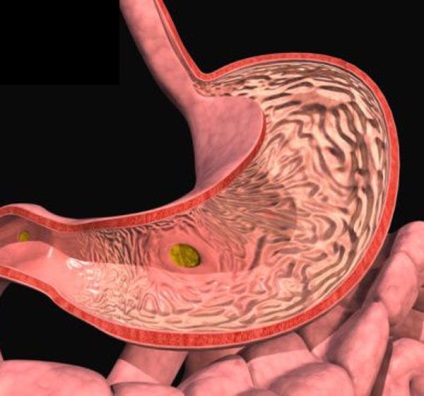

Modern osztályozás lehetővé teszi a polipok osztani két fő csoportba sorolhatók. Ez adenomás és hyperplasticus polipok. Az viszont, köztük számos faj, melyet érdemes megemlíteni ebben a cikkben.

Adenomatous polip - egy viszonylag ritka, de nagyon fenyegető daganat, ami fajul rák. Mint általában, ez nem jár együtt a baktériumok jelenléte a gyomorban, de lehet az oka, hogy perzisztens gastritis. A kezelés mindig operatív annak érdekében, hogy elkerüljék a degeneráció polipok a rák.

Giperplaziogenny polip - a tumor a formájában a „karfiol”, amely úgy tűnik, ha a páciensnek károsodott funkciója a nyálkahártya mirigyek a gyomor.

Polip antrum - ez elég gyakori abnormális proliferációja, amely lokalizált alsó testrész. Gyakran hasonlít egy adenoma és található egy közel alapon. Ajánlott műtét.

Endoszkópos műtét eltávolításával jár kis tumorok, amelyek székhelye a falakon a gyomor. Az endoszkóp áthalad a száj és a polip lokalizációs zóna. Gyalog daganatok dob diathermia hurkot levágja a polip, és ezzel egyidejűleg kiégethetik helye annak előfordulása. Ha az oktatás kevesebb, mint 0,5 cm, a markából biopsziás fogó és eltávolítjuk.

Általában egy darab szövetet feltétlenül küldött szövettani vizsgálatra, hogy meghatározzák a természet a kinövések. Ha ez adenomatózus polipok, akiket a kötelező konzultációt az onkológus. Cardia gyomorpolipok is veszélyesek, amelynek minden esélye, hogy kapcsolja be a rosszindulatú daganat, így a betegnek szüksége van egy kötelező biopszia és ajánlásait az onkológus.

Ha daganatok sok van, és méretük több mint 1,5 cm, célhoz kötött hasi sebészet - polypectomia. Ez részét eltávolítják az érintett polipok. Általában szövettani vizsgálatot azonnal el kell végezni, és ha az eredmények azt mutatják, hogy a daganat nem rákos, a gyomor lezárjuk. Ha a tumor rosszindulatú természetűek, hogy fennáll annak a valószínűsége, hogy a gyomor kell majd teljesen eltávolítjuk. Különösen a cardia polipok általában fajul a rák, így különös figyelmet igényelnek.